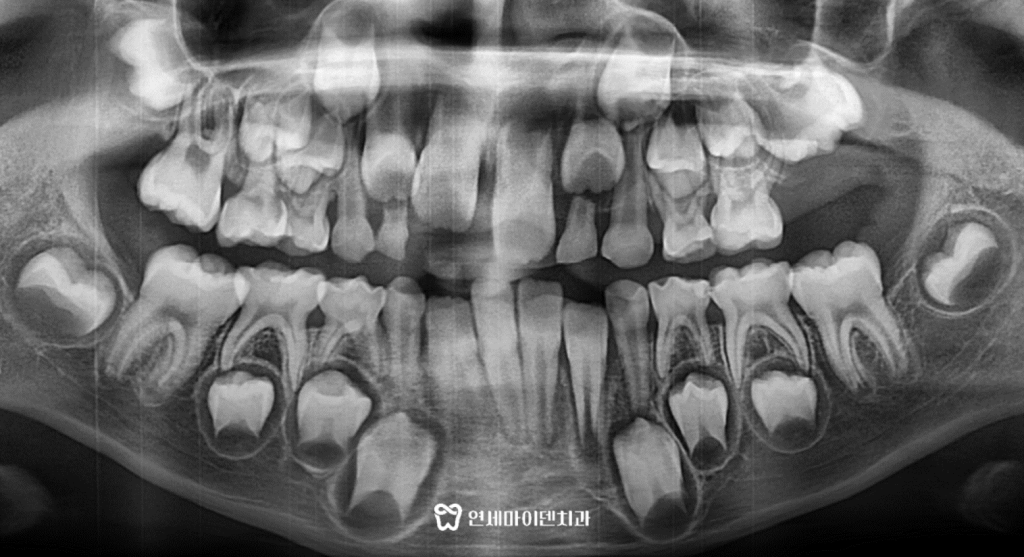

먼저 정확한 치아의 상태를 확인하기 위해

파노라마 방사선 촬영을 진행했습니다.

두번째 아래 앞니 유치는 빠지고

아래 영구치가 조금씩 올라오는 중인게 보입니다.

윗니는 아직 맹출되지 않았지만

다행히 다른 치아들은 큰 문제없이 자라고 있었습니다.

추가로 옆모습 방사선을 촬영한 뒤 정밀 교정진단을 통해

환자의 해부학적 구조를 파악합니다.

이 환자분은 윗니가 아직 나와있지 않은 상태를 감안하더라도

아랫니가 윗니 앞으로 많이 솟아올라와 있었습니다.

이 때문에 아랫입술도 확연히 더 나와보이고 있습니다.

정밀진단을 통해 위턱보다 아래턱이 골격적으로 발달한

3급 부정교합, 즉 주걱턱 상태를 확인한 뒤 치료 계획을 세웠습니다.